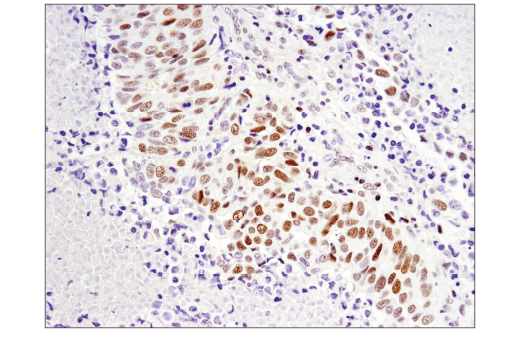

Immunohistochemical analysis of paraffin-embedded human infiltrating ductal carcinoma of the breast using SLFN11 (D8W1B) Rabbit mAb.

Immunohistochemistry Image 1: SLFN11 (D8W1B) Rabbit Monoclonal Antibody